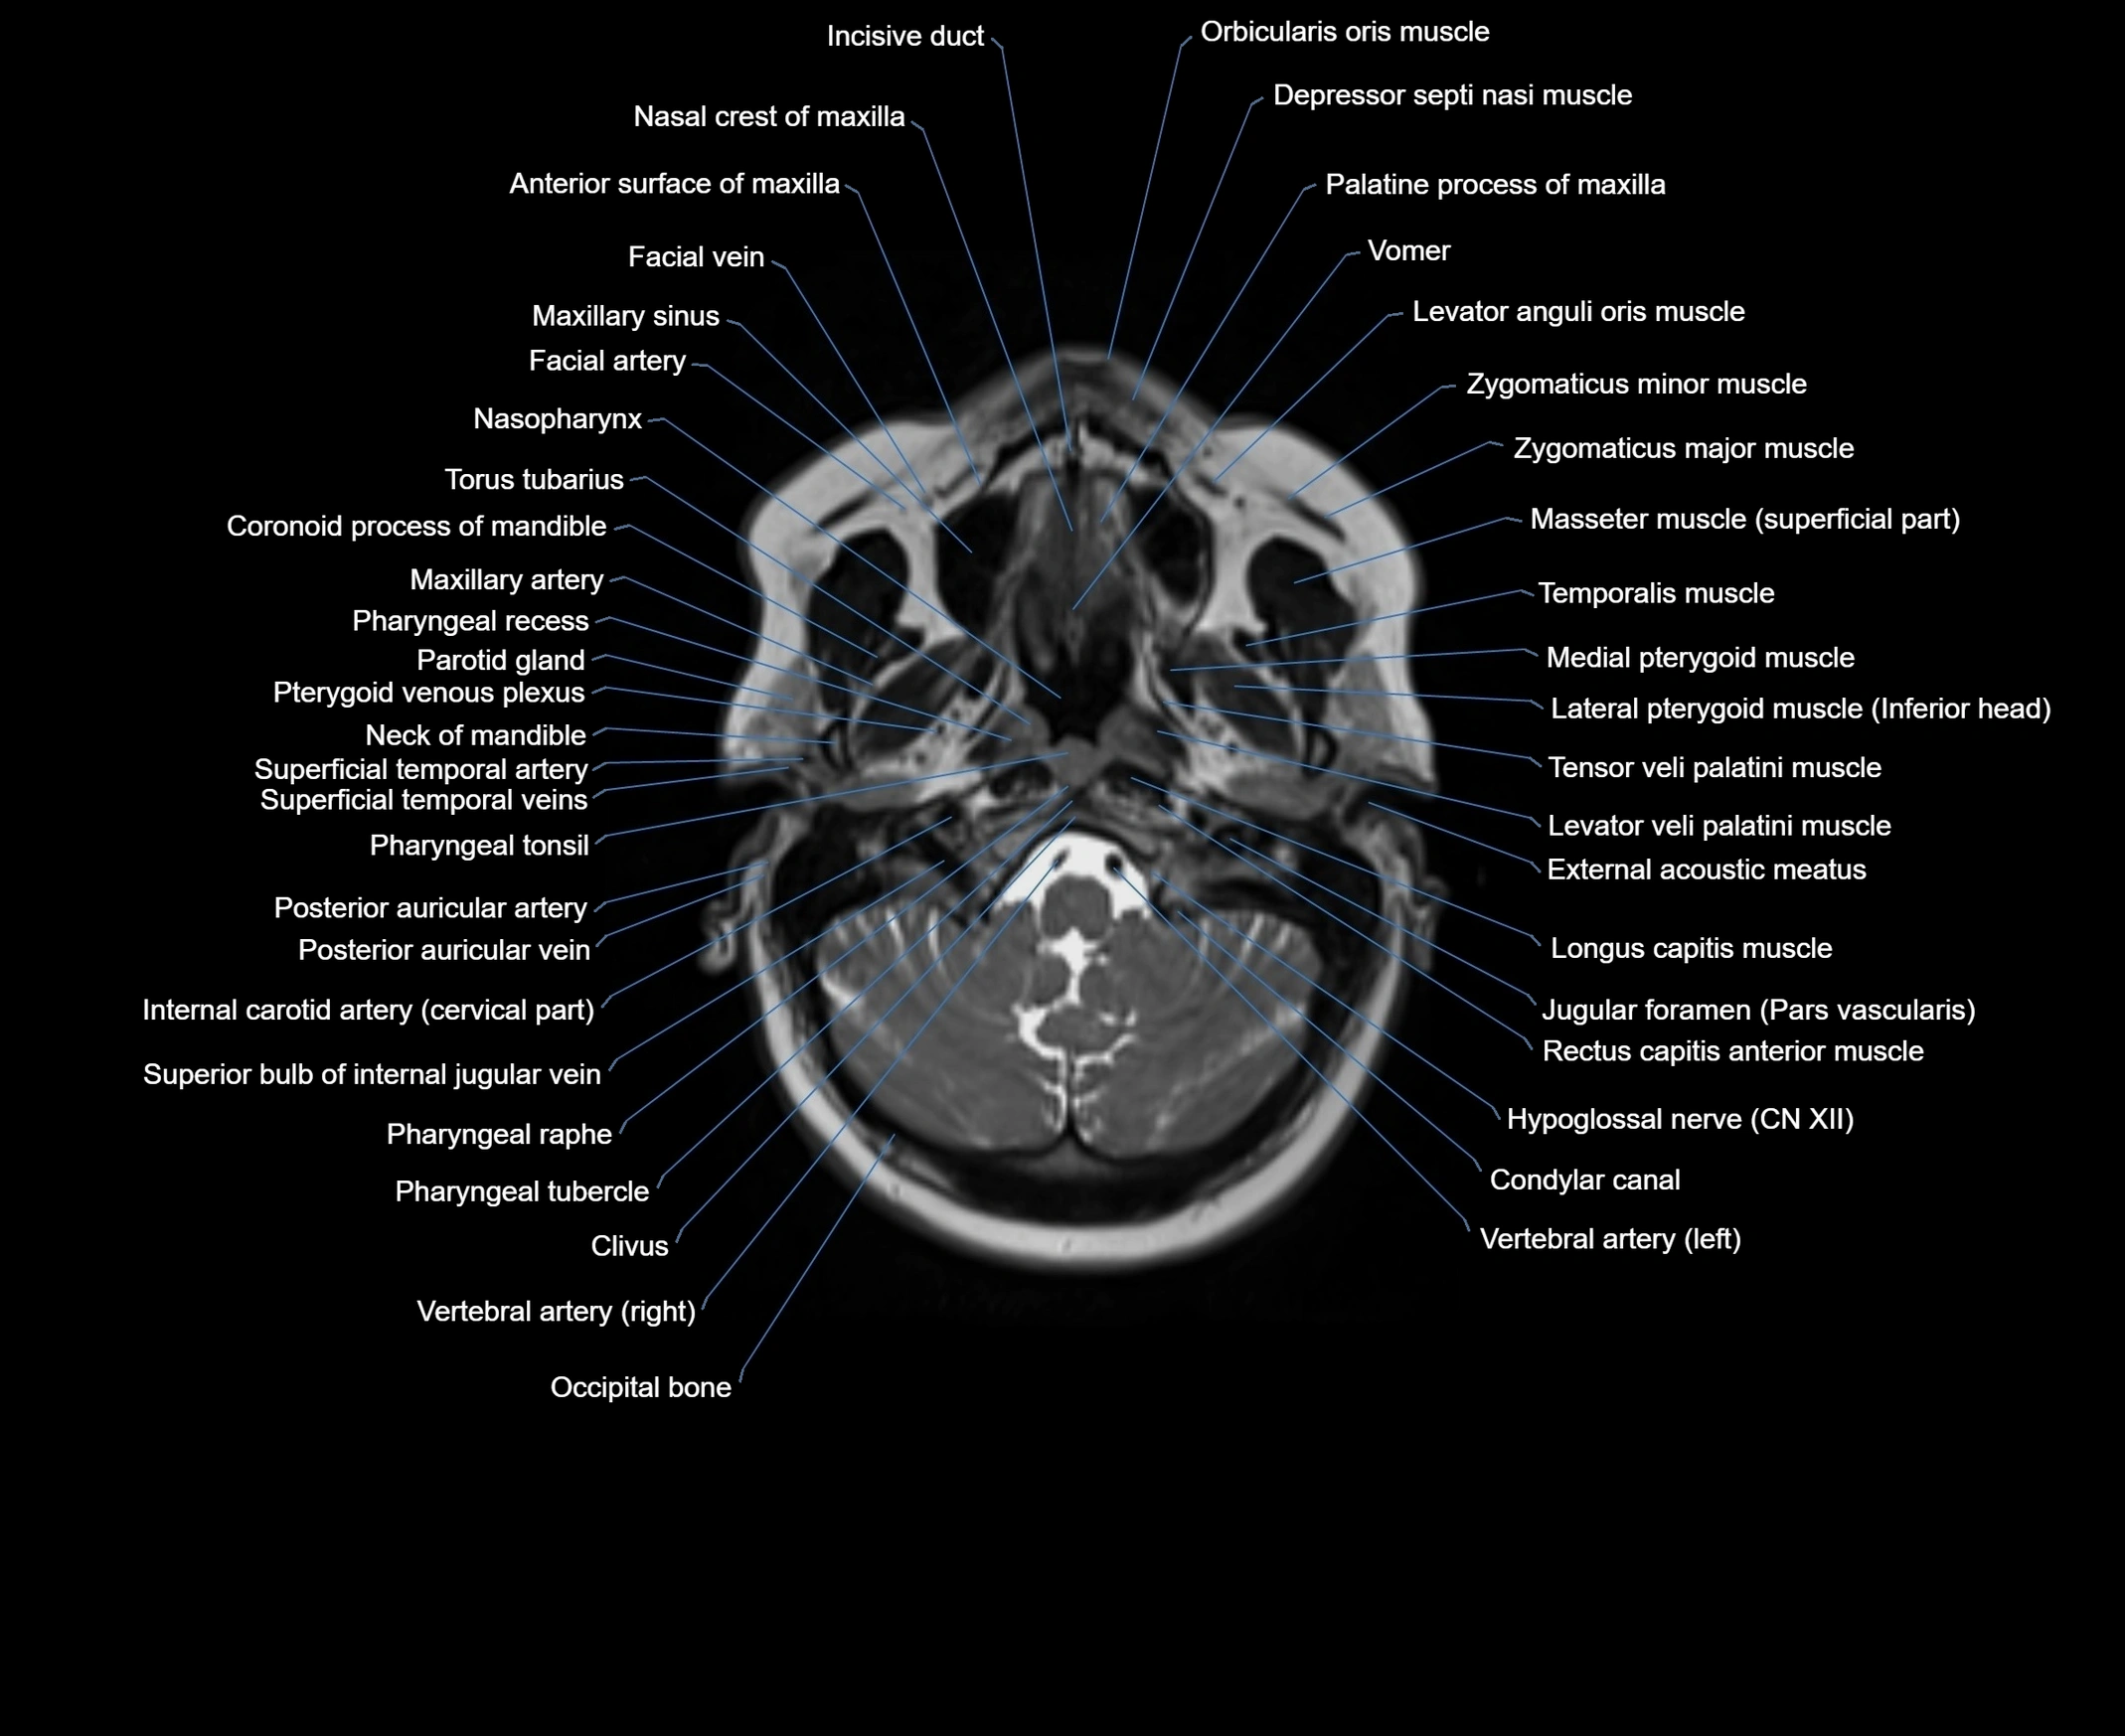

MRI images